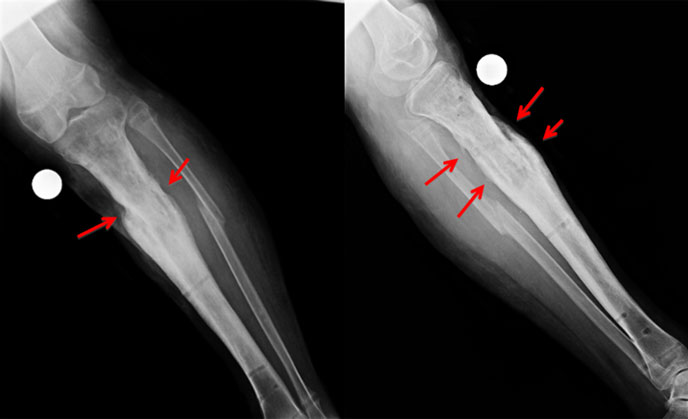

| 2 months |

| 2 months on, he continues to improve. The x-rays show signs of healing. There is formation of bridging callus. |

| After fixator removal |

| The x-rays right after fixator removal. The callus is well seen (red arrow) bypassing &bridging the nonunion site. |